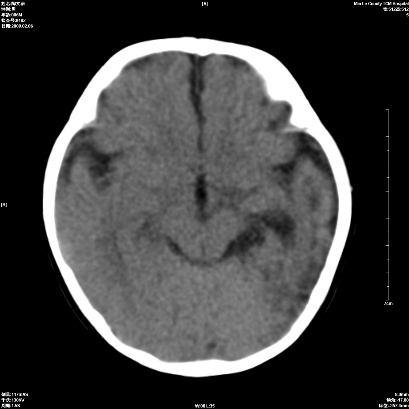

以下是引用wxq2008在2009-2-6 17:01:00的发言:[br]hie后遗症脑萎缩。

以下是引用学医在2009-2-6 21:45:00的发言:[br]hie后遗改变